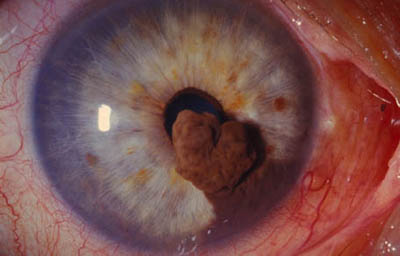

Melanoma del Iris

Es el tumor maligno primario más frecuente del Iris con riesgo de metástasis y muerte; representa aproximadamente el 5% de todos los melanoma uveales, no tiene predilección de género y es mas frecuente en Iris de color claro; la edad promedio de compromiso está alrededor de los 50 años.

Clínicamente se manifiesta como un tumor circunscrito o difuso.

El circunscrito, es una masa solitaria nodular en el estroma del Iris, con variables grados de pigmentación, con vasos nutricios intrínsecos en el estroma o dentro del ángulo. (31,32,33)

Melanoma sólido nodular del Iris

Archivo Fotográfico Dr. Francisco Barraquer.

Melanoma sólido nodular del Iris

Archivo Fotográfico Dr. Francisco Barraquer.

Melanoma sólido nodular del Iris

Archivo Fotográfico Dr. Francisco Barraquer.

Vista frontal del Melanoma sólido

Archivo Fotográfico Dr. Francisco Barraquer.

Melanoma sólido nodular del Iris con lente de Gonioscopía

Archivo Fotográfico Dr. Francisco Barraquer.

Angiografía del iris